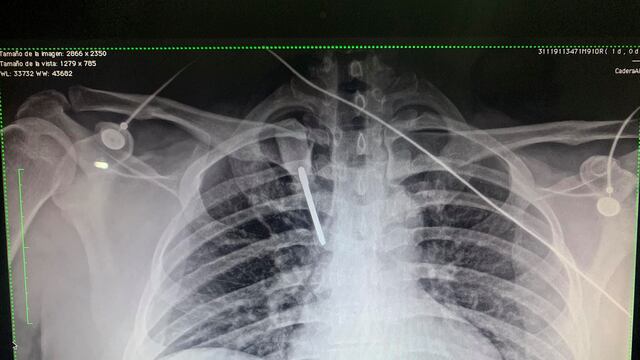

De momento sintió un golpe en el pecho y lo tumbaron. Luego se acercó un militar y un vigilante que le pidieron que no se moviera porque tenía un desarmador clavado.